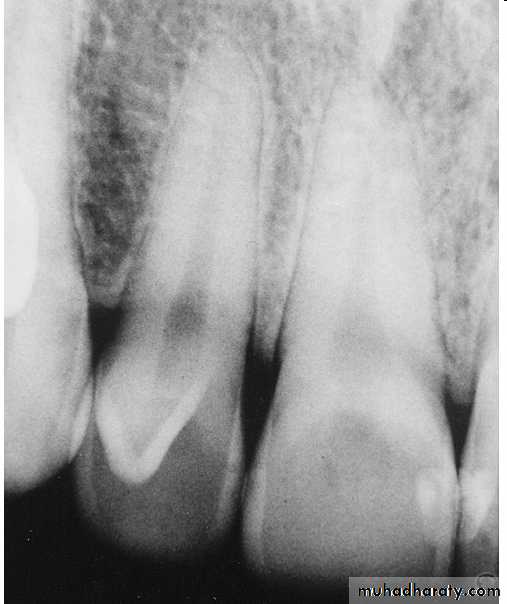

*Type I:it is confined within the crown of the tooth and does not extend beyond the level of the external CEJ. *Type II :extends below CEJ ends in a blind sac, may or may not communicate with adjacent dental pulp. *Type III:extends through the root and communicates laterally with the periodontal ligament space through a pseudo-foramen or at the apical foramen . There is usually no communication with the pulp, which lies compressed within the root.*Most cases of dens in dente are discovered radiographically. It is more radiopaque than the surrounding tooth structure and can easily be identified.